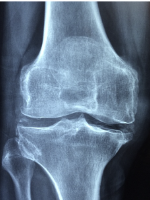

무릎 관절염 증상 무릎 관절염 원인 치료방법 관리방법 등 무릎 관절염에 관한 정보를 정리해드리도록 하겠습니다. 무릎 관절염은 무릎 관절에 염증이 생기는 질환으로, 통증과 붓기, 운동장애 등의 증상을 유발합니다. 무릎 관절염에는 여러 가지 원인이 있지만, 가장 흔한 것은 퇴행성 관절염입니다. 퇴행성 관절염은 노화나 과부하로 인해 무릎 연골이 닳아나가는 과정에서 발생하는 질환입니다. 연골은 무릎 뼈 사이에 있는 연한 조직으로, 뼈의 마찰을 줄여주고 충격을 흡수하는 역할을 합니다. 연골이 손상되면 뼈와 뼈가 직접 부딪치게 되어 통증이 생기고, 염증 반응이 일어나서 붓기가 발생합니다.

무릎 관절염 원인

무릎 관절염의 가장 흔한 원인은 나이가 들면서 연골이 자연적으로 닳아가는 퇴행성 변화입니다. 퇴행성 관절염은 주로 중장년층에게 많이 나타나며, 여성에게서 더 흔합니다. 퇴행성 관절염은 무릎 외에도 손, 엉덩이, 발목 등 다른 관절에도 생길 수 있습니다.

무릎 관절염의 다른 원인으로는 외상, 비만, 유전, 직업, 스포츠 등이 있습니다. 외상으로 인해 무릎 관절이나 연골이 손상되면 골관절염이 생길 수 있습니다. 비만은 무릎 관절에 부담을 주어 연골의 손상을 촉진합니다. 유전적 요인은 연골의 구조나 품질에 영향을 줄 수 있습니다. 직업이나 스포츠로 인해 무릎 관절을 과도하게 사용하거나 반복적인 부상을 입으면 골관절염이 생길 수 있습니다.

또한, 선천적으로 무릎 관절이나 골격 구조에 이상이 있거나, 세균성 관절염이나 내분비 질환과 같은 다른 질환으로 인해 이차적으로 골관절염이 생길 수도 있습니다.